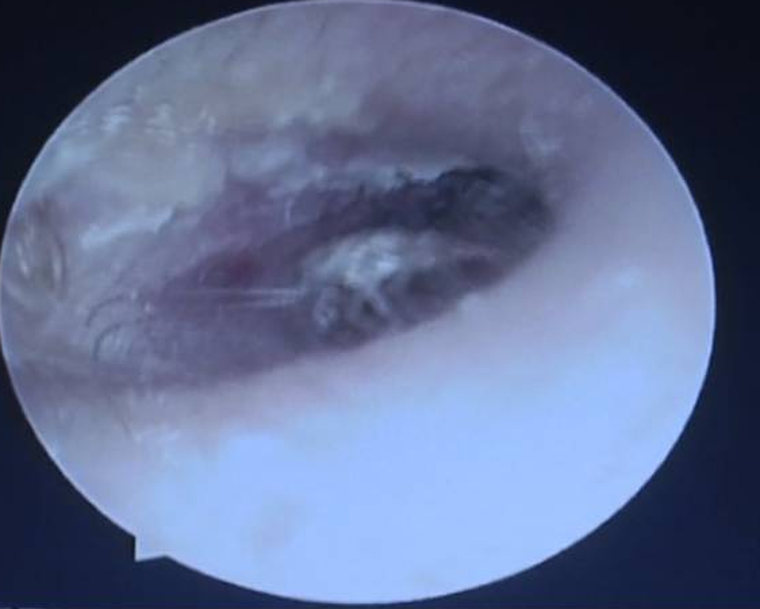

Cuando los médicos examinan a un hombre que se queja de dolor en el oído en la ciudad de Dongguan, en la región del sur de China de la provincia de Guangdong, descubrieron que la fuente de su agonía era una cucaracha. Peor aún, el insecto había dado a luz a 25 bebés dentro de su oído.

El insecto medía 0.3 pulgadas de largo y había dado a luz a 25 cucarachas más en el interior del conducto auditivo externo. Los médicos coincidieron que si este sujeto hubiese dejado pasar más tiempo, el oído hubiese sido destruído por las cucarachas. Mirá el impactante video: